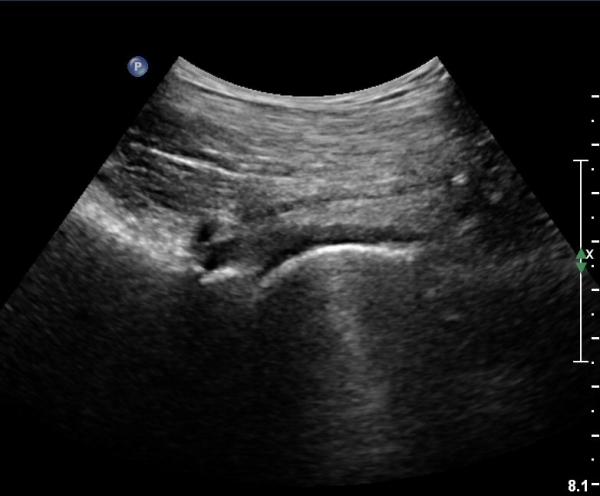

[¾ûµ¢ÀÌ] ¾ûµ¢ÀÌ °üÀý¼ø ÆÄ¿­ÀÇ ÃÊÀ½ÆÄ°Ë»ç(ultrasonography of labrum tear of hip joint)

Sonography of the Acetabular Labrum Visualization of Labral Injuries During Intra-Articular Injections

What is the role of clinical tests and ultrasound in acetabular labral tear diagnostics?

Sonographic evaluation of anterosuperior hip labral tears with magnetic resonance arthrographic and surgical correlation.